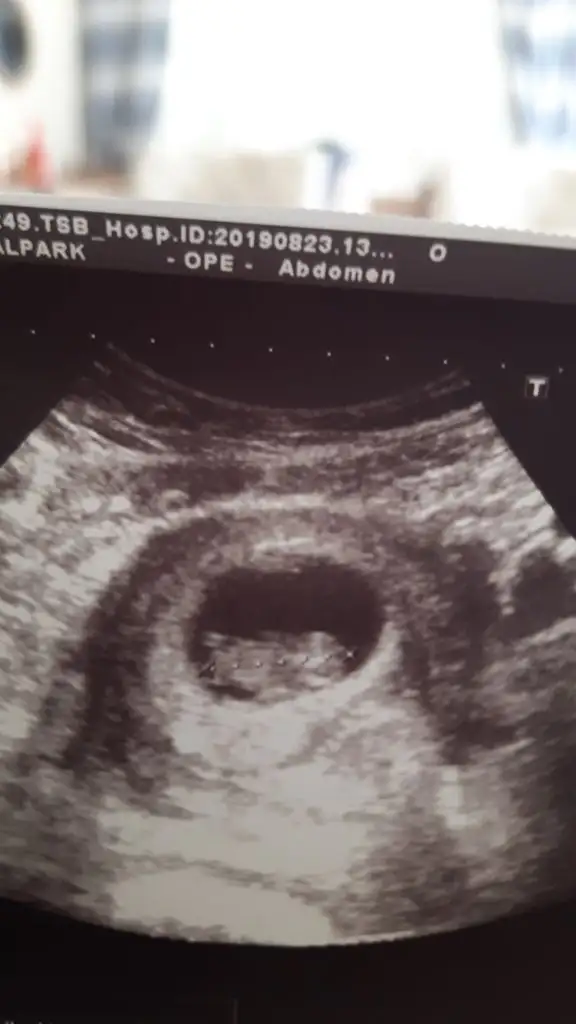

KizzMerhaba bizim cinsiyetimize de bakarmısınız

KizzMerhaba yorumlayabilirseniz çok sevinirim.

Usg hic net degil cnm dr lar genelde bu haftalarda erkekse tahminde bulunuyorlar ama inan ben bisey goremedim icimden kiz demek gecti ama dedigim gibi usg ye gore tahmin degilSat 9+2 usgye gore 10 hftalik. Doktor kucuk bi tahminde bulundu. Siz de bi tahminde bulunurmusunuz

Erkek gibiMerhaba sırf bu konu için üye oldum bize de bakabilir misiniz

Erkek diyorumMerhaba bizim cinsiyetimize de bakarmısınız